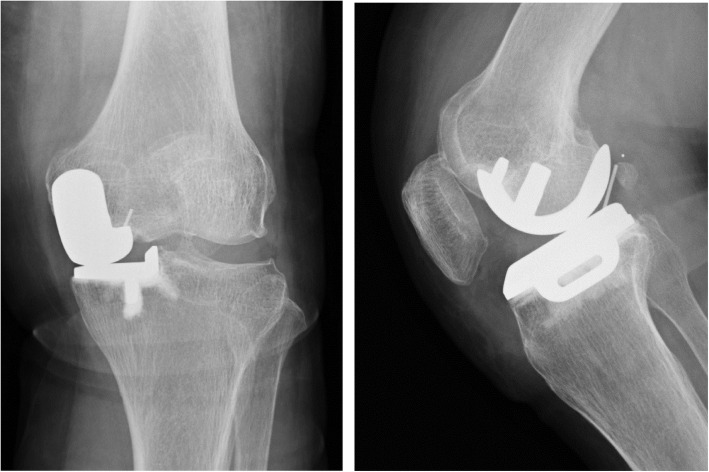

Fig. 2.

Radiographs of case 1 showing the bearing posterior dislocation

At 13 months postoperatively, she had sudden and severe knee pain while asleep. She could not walk, so she had to be brought to our facility in an ambulance. The meniscal bearing was posteriorly dislocated, as shown on the radiographic images (Fig. 2). We could not succeed in closed reduction; therefore, we performed surgical intervention. During the revision surgery, we observed the subsidence of the femoral component. The femoral component could easily be retrieved because of the loosening of the femoral component. In addition, there was no bone attached to the undersurface of the retrieved femoral component (Fig. 3). We implanted the same small-sized cemented Oxford femoral component, and the 8-mm thick bearing was inserted (Fig. 4). One year after the revision of UKA, her knee was pain-free and had a ROM of 0° extension to 140° flexion. She had no femoral migration and bearing re-dislocation.